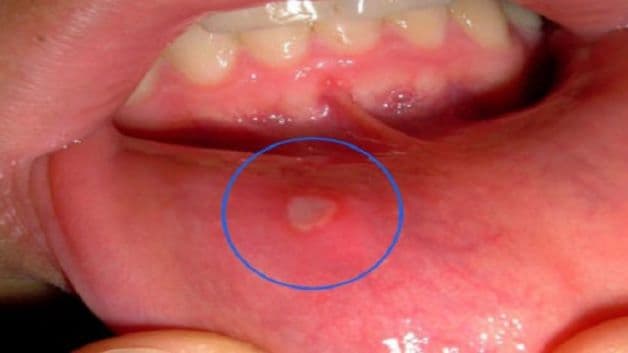

Khi mắc loét áp tơ miệng, trẻ sẽ xuất hiện các tổn thương loét theo hình tròn hay hình ô van, lõm xuống, bên trên phủ giả mạc trắng và xung quanh là bờ viền đỏ. Vùng tổn thương gây cảm giác đau, nhất là khi bé ăn thức ăn nhiều chu hay mặn. Nếu được hỗ trợ điều trị kịp thời, vùng tổn thương của bé sẽ dần khỏi sau từ 4 – 14 ngày, tùy tình trạng và thể trạng của trẻ.

Loét áp tơ miệng là một trong những bệnh viêm lợi cấp hay gặp ở trẻ